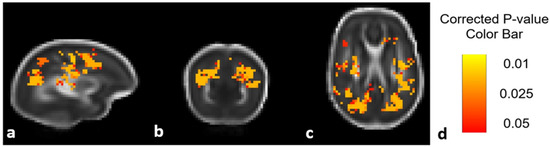

Figure 2 shows an unadjusted DTI ANTs analysis comparing diffusion values (in this case MD) between treatment groups prior to additional statistical analysis (including corrections for sex and scanner type) described in the Methods section above.

Figure 2. DTI comparison of Epo-treated and placebo-treated groups using ANTs analysis. MD differences seen in the sagittal (a), coronal (b), and axial (c) views. Highlighted areas signal regions in which the Epo treated group had significantly higher MD values compared to the placebo group prior to evaluation with multiple corrections. p-value color bar shown in (d).